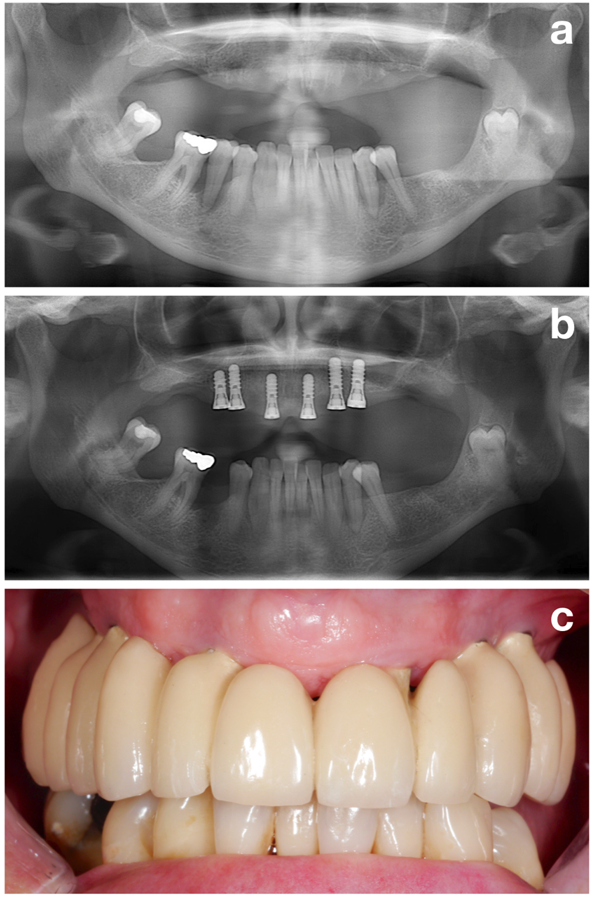

Im ersten Teil (also in der Vorbehandlungsphase) werden alle potenziellen Risikofaktoren ermittelt, um den Patienten bestmöglich auf die spätere Implantation vorzubereiten. Der Fokus liegt dabei jedoch auf einem der wichtigsten Aspekte, nämlich dem Schaffen eines stabilen parodontalen Zustandes (Abbildung 2).

Abschließend lässt sich festhalten, dass ein stabiler parodontaler Zustand neben anderen Zielen wie der Raucherentwöhnung oder einer einwandfreien Mundhygiene (Abbildung 3) einer der wichtigsten Aspekte im Rahmen der Vorbehandlungsphase darstellt. Dieser Zustand sollte vor der Implantation erreicht werden.